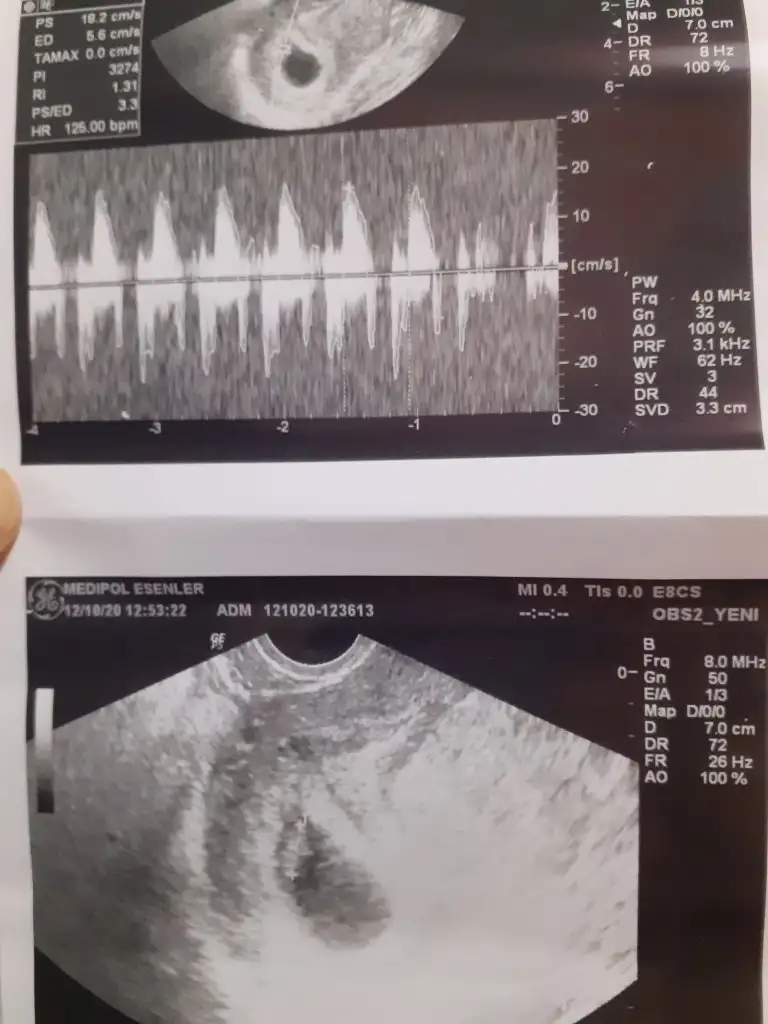

Evet küçükmüş annesi aynen sayılı günler gelir geçer. Progestanı ağız yoluyla alıyorum. 2 günde bir doktordaydım hep kanama yaşadım çok zor her tuvalette iç çamaşırıma bakıyordum kan var mı diye. Fırsat buldukça dinlenmeye çalış sen. Cinsiyet tahminin var mıEvet 3.5 yaşında kücük malesefrabbim yardımcı oluyor insana inşaallah bende atlatırım saglıklı bir şekilde progestanı alttanmı kullanıyordunuz acaba agızdanmı?

Kendime mi cinsiyet tahminim varmı?Evet küçükmüş annesi aynen sayılı günler gelir geçer. Progestanı ağız yoluyla alıyorum. 2 günde bir doktordaydım hep kanama yaşadım çok zor her tuvalette iç çamaşırıma bakıyordum kan var mı diye. Fırsat buldukça dinlenmeye çalış sen. Cinsiyet tahminin var mı

Aynen tutmayabiliyormuş ama kesin değil tabiki doktorun söylediği de. İnşallah gönlünüzden ne geçiyorsa o olur. Bende 8.haftayı doldurduğumda hislerim oluşmaya başlamıştı. Dün gece iç çamaşırım baya bir ıslaktı sanki idrarımı yapmışım gibi ki yapmadım aklıma bebeğin sıvısı mı acaba diye korka korka durdum. Bugün çok dua ettim hala sağlıklıdır diye anladım ki evlat evlatmış kızı erkeği yokmuş.Demekki annelerin hisleri herzaman tutmayabiliyormus:) benim oğlumdada düşük tehlikem vardı bundada var ama Daha ileri derecede, oğlumun hamileliğini hic anlamadım desem yeridir bundada farklı olarak midem biraz agrıyor Gün boyu sürebiliyor yoksa aynı ilerliyor suan içinAma ben nedense cinsiyet tahmini yapamıyorum bunda ,oğlumda erkek hissetmiştim eşimde aynen o şekil hissetmişti bundada erkek diyor o ama ben hissedemiyorum

Aynen canım doktorumla görüştüm gelen suyun devamı yoksa önemli değilmiş çok şükürKesinlikle Rabbim neyi verirse kabuldür insanların cocukları olmuyor malesef bizlere nasip etmiş Cok sükür o yüzdeN o neyi verirse güzeldir baş üstüne